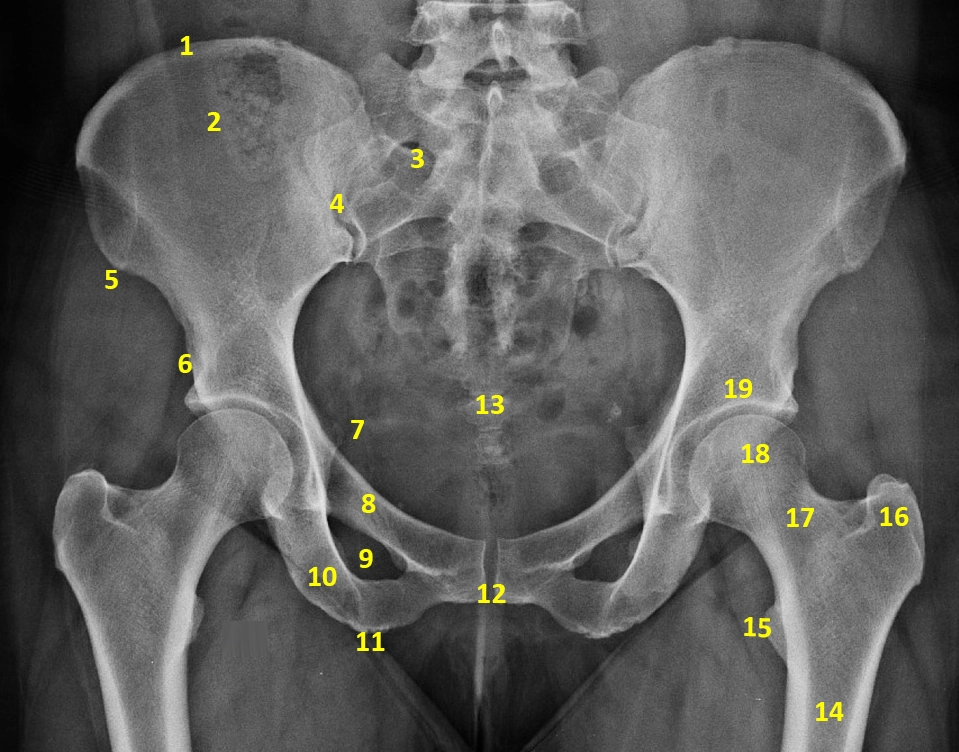

X Quang xương chậu

16/03/2026